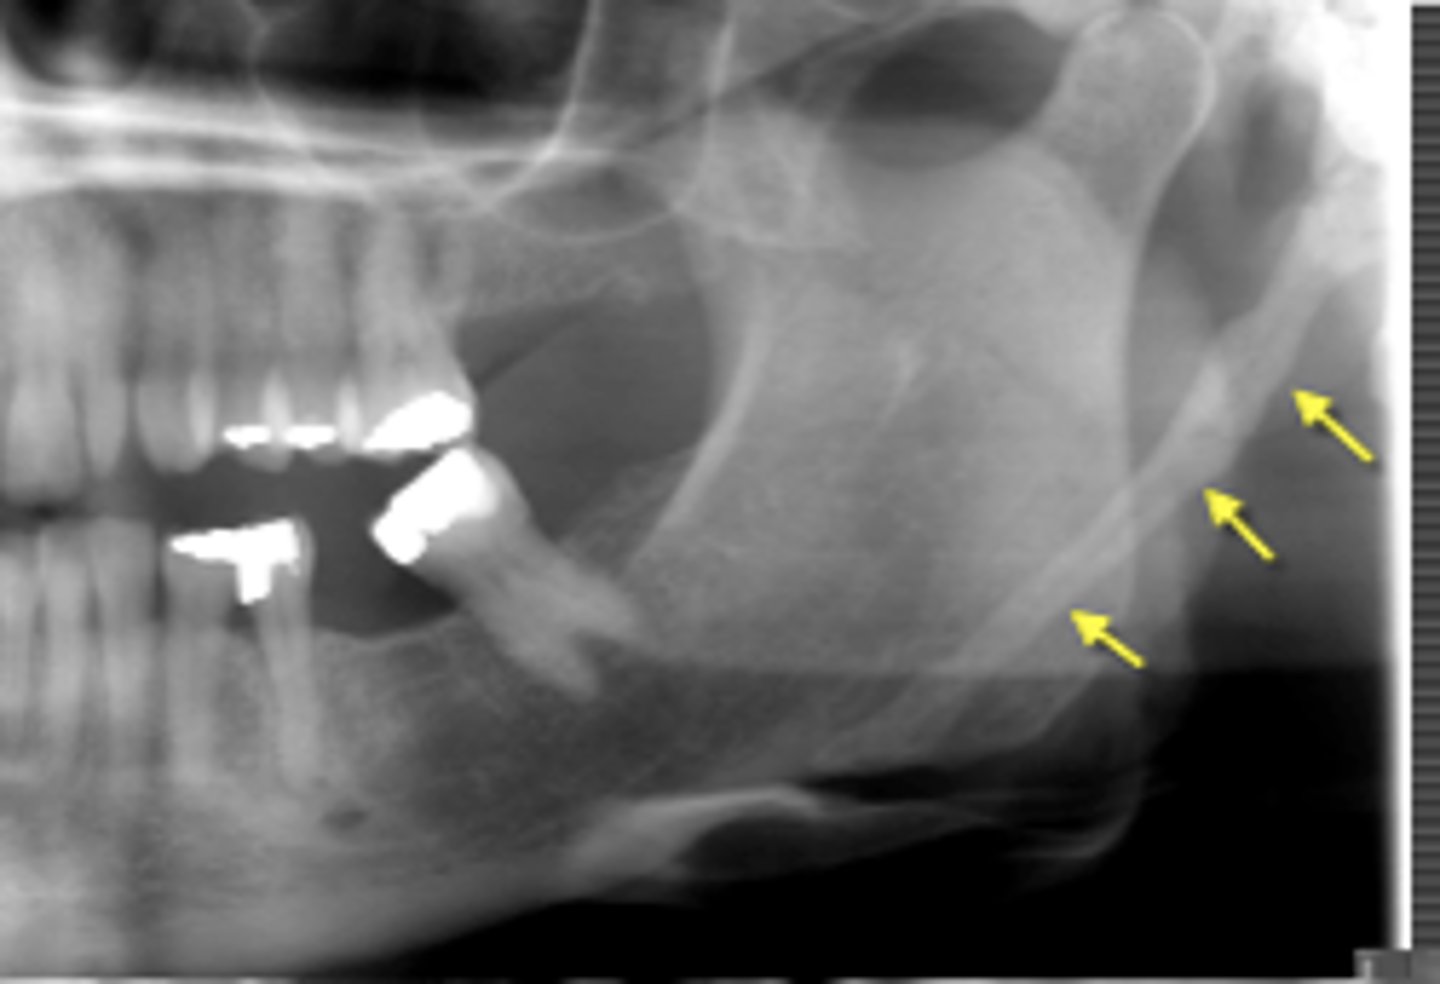

Name of disease:

on a pan view looks like a bone under the angle of the mandible. It is elongation and clarification of the temporal ____ at the back of the throat that occurs after a tonsillectomy or trauma.

eagle syndome

temporal styloid process

name of disease :

elongatoin and minerlaized of the styloid process that impinges on the carotid arteries and nerves. Patient ocmplains of aunilateral neck pain when turning thier head, possible sore throat, dysphagia.

Tx?

Mild cases:_____

severe cases:____

carotid artery syndrome

mild cases: none except reassurance or local corticosteroids to relieve pain

severe caess: surgical intraoral excision of the process